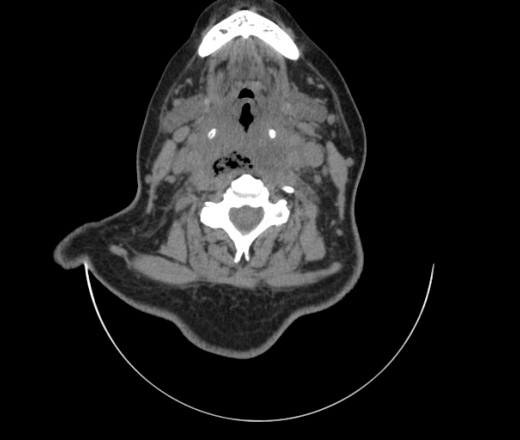

Женщина поступила в х/о спустя 4 дня после того как при употреблении карася подавилась костью.

Наличие газа в средостении на протяжении тел С2-С6 (медиастинальна эмфизема); рыбная кость на уровне тела С6.

При всем уважении, но говорить о медиастинальной эмфиземе, оценивая мягкие ткани шеи, как-то слишком резко. На мой взгляд, это ретрофарингеальное пространство.

Согласен с Вами; конечно, наличие газа в клетчатке ретрофарингеального пространства (затмение с опечаткой..). К сожалению, процесс "продвигается" к медиастиниту. Но почему никто, не отмечает наличие рыб. кости; или это для Всех очевидно?

Кость то мы сразу выявили, размеры где то 17*2мм, но ее так и не получается найти в этой каше